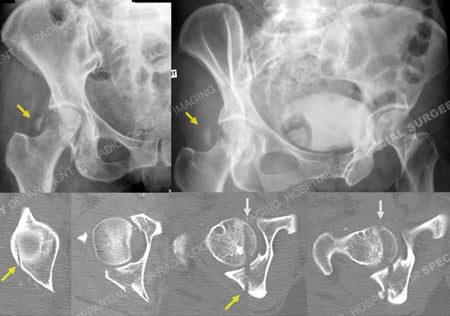

X-rays (top) revealing a right-sided Pipkin IV femoral head fracture and associated Posterior Wall acetabular fracture (yellow arrows) and CT scan images (bottom) further delineating the fracture patterns (femoral head fracture is indicated with grey arrows).

A 64-year-old female was involved as a passenger in a high-speed motor vehicle accident while on vacation in Nicaragua. She was taken to a local hospital and diagnosed with a right-sided posterior hip dislocation that was closed reduced. She also had an associated right-sided Pipkin IV Type fracture of the femoral head with associated Posterior Wall Type fracture of the acetabulum. After placement of skeletal traction she was transferred to the care of Dr. David L. Helfet at the HSS Orthopedic Trauma Service through a medical flight facilitated through her travel insurance. Open reduction and internal fixation (ORIF) was performed through a Kocher-Langenbeck surgical approach with an anterior surgical hip dislocation. The Posterior Wall fracture was reduced and fixed with one-third tubular and pelvic reconstruction plates and screws. The femoral head fracture was reduced and fixed with sub-articular screws and preservation of the blood supply, reduction, hip stability, and adequate hardware placement was confirmed. At the time of her latest follow-up at 5 months radiographs reveal healed acetabular and femoral head fractures and maintenance of reduction with mild degenerative changes in the hip joint.